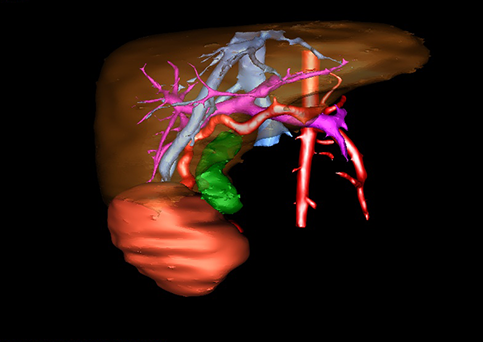

图1 位于肝右的叶肝母细胞瘤, 6个月,男婴

目前常用的检查方法有B超检查、CT、MRI、血管造影等。与其它的腹部肿块的诊断不同,对于小儿肝母细胞瘤血管造影具有重要的意义,可以作为手术前介入治疗的手段,也可为手术提供非常有效的影像学指导,但技术要求高,操作较复杂,且给患儿带来一定的痛苦。近年借助计算机辅助手术系统进行CT原始影像三维重建、手术规划和计算机虚拟手术技术,为精准肝脏手术提供了极为有效的技术支持。

近年来由于数字医学的发展,基于可视化三维重建技术的计算机辅助手术系统极大推进了小儿肝脏肿瘤的精准手术的进步。可以立体透视肝脏解剖、精确掌握肝段的边界、精确测算肝段乃至任意血管所支配的功能体积、准确定位病灶及其与邻近血管的解剖关系,最终对不同手术方案进行比较、筛选和优化。因此,计算机辅助手术规划系统是实现精准肝切除的有力辅助工具,是未来数字外科、精准外科等21世纪外科新理念的重要技术支撑。

计算机辅助手术规划系统具有良好的操作可行性、计算准确性和三维显示效果,可半透明、交互式显示真实的肝内立体解剖关系和空间管道变异,准确计算肝内管道的直径、走行角度,两点间的垂直距离,和任意血管的支配或引流范围等传统二维影像无法获取的信息,有助于实施个体化手术,提高了手术的确定性、预见性和可控性。计算机辅助手术规划系统可直观显示预留肝脏的结构和功能,并可通过虚拟切割功能辅助术者对手术方案进行蹄选和优化,系统评估手术风险和制定对策,改变了部分二维规划的术式和切除范围,使部分二维规划认为不能切除的患者成功手术,提高了手术的根治性、安全性和病变的可切除性,更加符合精准肝脏外科的术前规划要求。详见第11章。